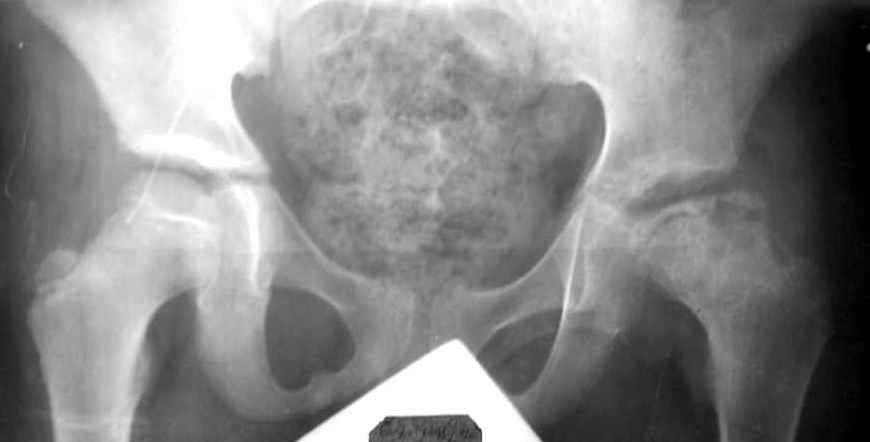

Мальчик 12 лет. Год назад по поводу асептического некроза, в субкапитальную область пересадил аутокостный трансплантат, взятый из Spina iliaca an.sup., на мышечной ножке m.sartorius.

На представленной рентгенограмме (лев. сустав) типичная картина последствия болезни Пертеса с уменьшенной высотой эпифиза. Процесс завершился и нет необходимости в дальнейшем использовании доп. средств опоры. Выраженных дспластических явлений нет. Позвольте пациенту жить без особых ограничений, но ежегодно проводите контрольный осмотр. АИФ.